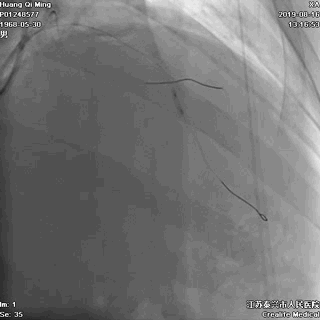

导丝通过病变

球囊扩张,PTCA

导丝通过病变抵达血管远段

8atm,2.0*20球囊行PTCA